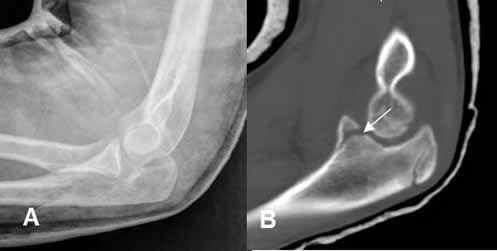

La TAC permite valorar lesiones en pacientes inmovilizados con yeso, férulas y otros elementos de fijación, sin disminuir la calidad de la prueba. En casos de elementos metálicos utilizar alto miliamperaje, ventanas de hueso y reconstrucciones, para tratar de disminuir los artefactos. Las reconstrucciones 3D son de mucha ayuda para la planificación del manejo, por parte del ortopedista. (1, 2). (Fig 20, 21 y 22).

Fig 20. Reducción de luxación.

A: Rx lateral. Luxación reducida y fijada con yeso.

B: TAC reconstrucción sagital. Después de la reducción se identifica fractura en la parte anterior de la coronoides, no sospechada en la Rx.